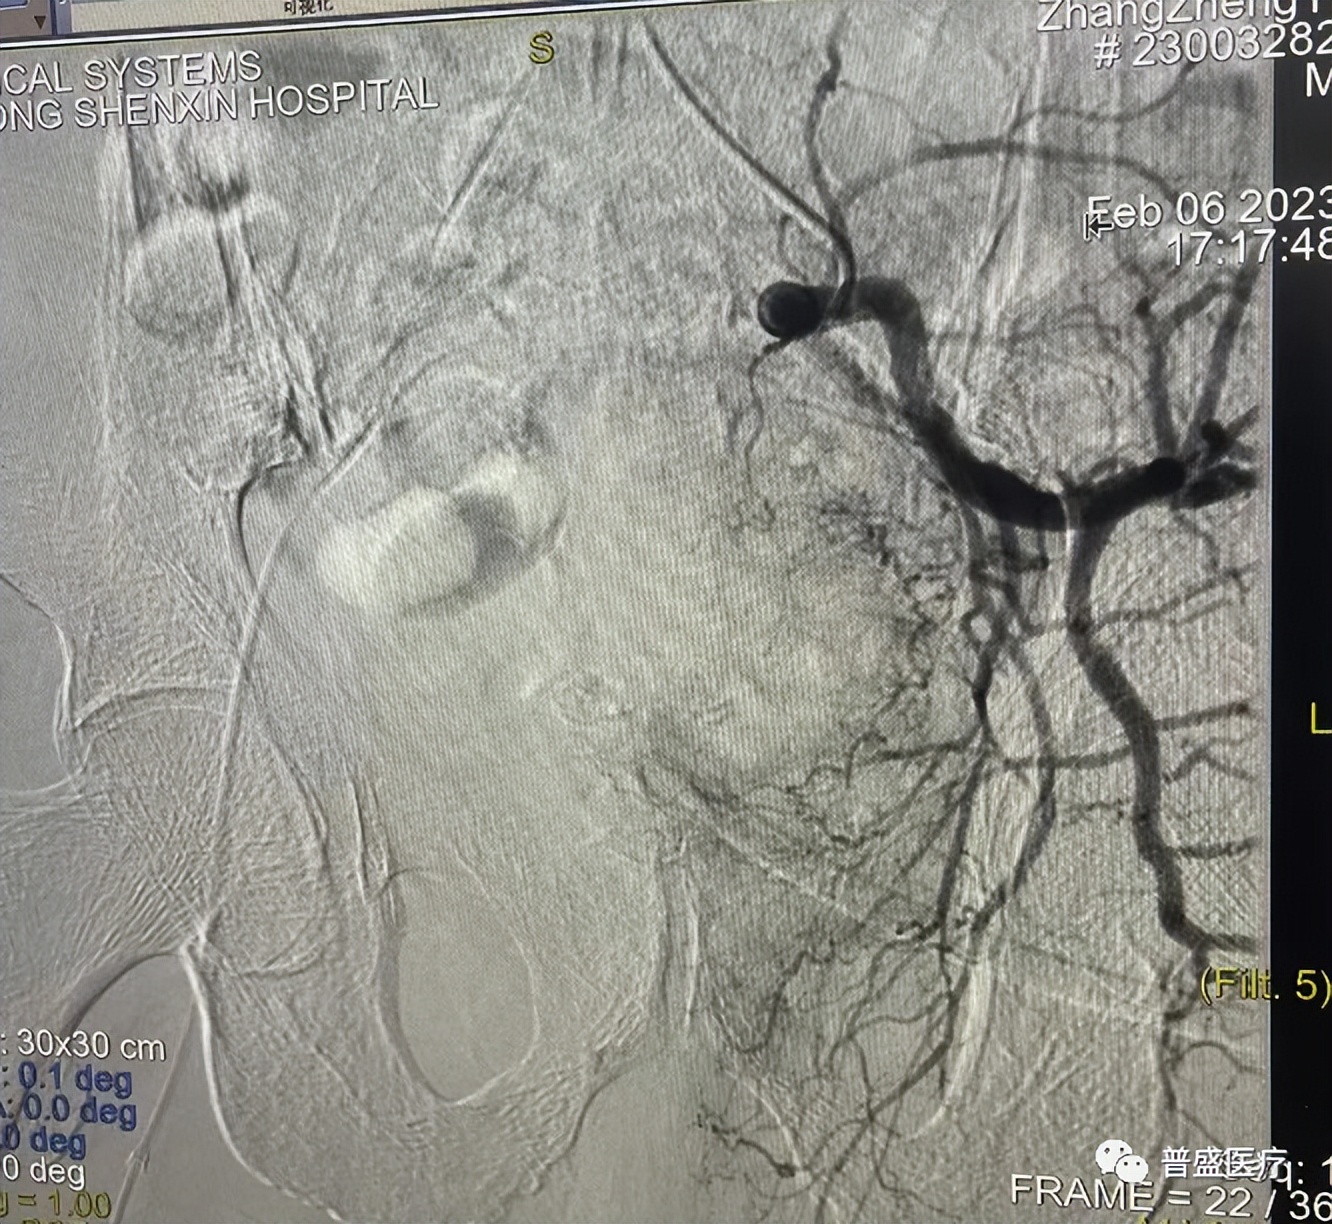

患者77岁,本地居民。确诊前列腺癌1+年,发现左下肢水肿1月,血尿,并患有骨继发恶性肿瘤。经过多学科专家会诊讨论,对病情进行了详细了解,一致认为,患者适合做微创介入手术治疗,通过与患者及家属沟通后,对患者术中可能出现的风险及术后并发症制定了详细的应急处理预案。

术中,通过明胶海绵栓塞左侧膀胱动脉后再造影确认化疗后目标动脉见血供阻断,血流逐渐消失;再次插入微导丝,进入左侧前列腺动脉再次造影确认后通过栓塞微球及明胶海绵栓塞目标动脉见血供阻断,血流逐渐消失,再次造影确认完善栓塞,手术结束。